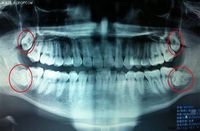

李洋 · 2016-10-10 04:17 - 卓老板聊科技VOL.9 當(dāng)牙齒出現(xiàn)了問題

大部分人過了25歲就會出現(xiàn)牙齒問題了,我就是個(gè)例子,春節(jié)前我的牙開始疼,連續(xù)去了幾次醫(yī)院,也和醫(yī)生聊了不少,這期節(jié)目想把聽到的這些知識和大家分享,也許對歲數(shù)大的人來說現(xiàn)在維護(hù)已經(jīng)有一些亡羊補(bǔ)牢了,但如果你現(xiàn)在還不到25歲,這期的內(nèi)容會很有用,但不論如何對我們的下一代都有用?!蹲坷习辶目萍肌罚?):當(dāng)牙齒出現(xiàn)了問題,3月2日首播音頻地址:點(diǎn)擊這里主播:卓克,微博:【香蕉樹上看著你笑】? ? 如果您感

卓克 · 2015-03-01 20:44